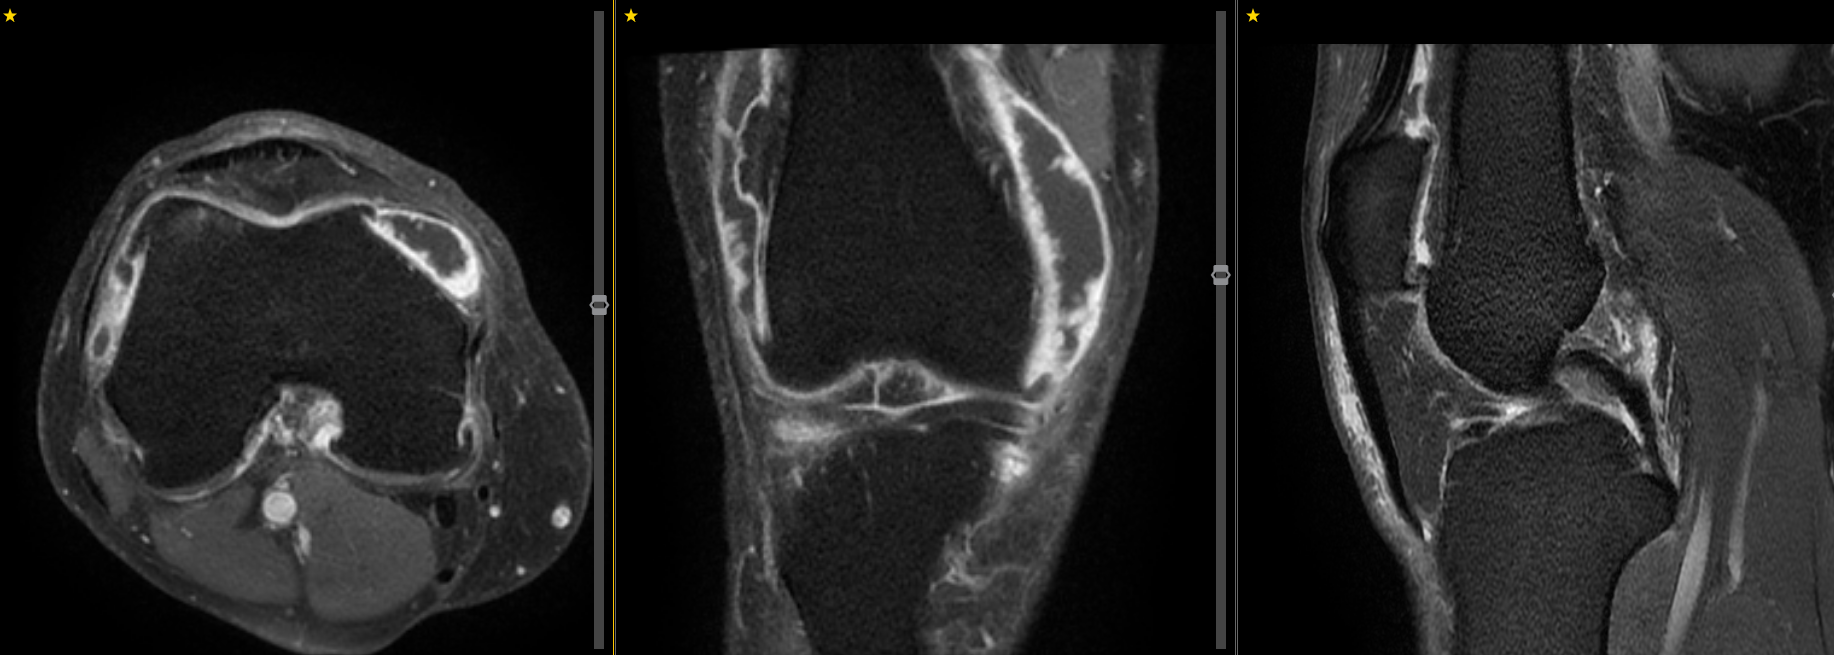

MRI angiography shows the genicular arteries supplying the knee and associated hypervascularity on the medial side. This hypervascularity is caused by neo-vessels as a result of inflammation, with further neo-nerves growing in and causing pain.

MRI knee with a post gadolinium T1FS sequence showing marked enhancement of the knee joint affecting the synovium with a small effusion. The hypervascularity demonstrated here is associated with neo-nerve growth, resulting in severe pain.

MR angiography showing the genicular arteries of the knee.

MRI demonstrates marked synovial hyperenhancement in a patient with knee osteoarthritis. A great target for TAME.